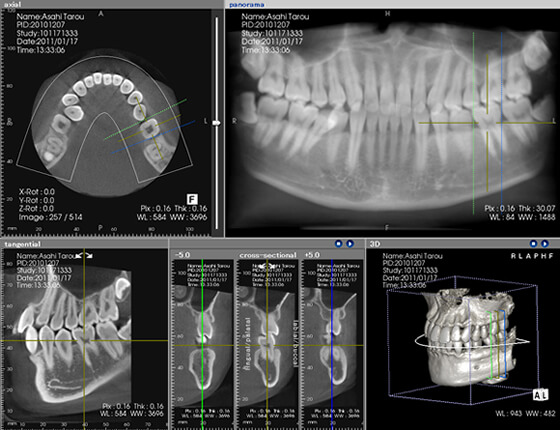

CT

CTは三次元の立体画像を撮影できる画像装置です。これを活用することで、一般的な二次元レントゲンでは見えなかった部位まで確認ができます。